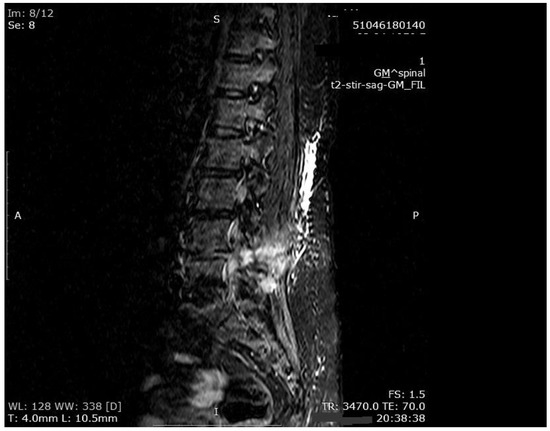

The mean number of total HBO2 sessions was 33 (±18.5) sessions. The HBO2 treatment was tolerated well by all patients except two. One patient had to receive analgesics (non-steroidal anti-inflammatories) before HBO2 sessions because she had severe back pain, and in one patient the treatment was interrupted for five days because of minor middle ear barotrauma. Improvements in clinical evaluations and laboratory findings were observed in all cases at the end of the HBO2 therapy. The mean erythrocyte sedimentation rate (ESR) value reduced from 76.1 (range, 6–129) to 45.7 (range, 5–81) mm/h, and the mean C-reactive protein (CRP) concentration reduced from 82.9 (range, 14–202) to 17.5 (range, 1–49.5) mg/L (normal limits; ESR: <20 mm/h, CRP: 0–5 mg/L). Infection resolution was adequately achieved in 12 of 13 patients on MR imaging at the end of HBO2 treatment or during the first month of follow-up (Figure 3, Figure 4 and Figure 5). There was no significant improvement in one patient. To extend the total clinical follow-up period up to three years (mean: 11 months; range, 1 month–3 years), telephone interviews were conducted to determine any recurrence of symptomatic clinical infection. No recurrence of infection, spinal instability, or deformity was seen in any patients.

Figure 4. MR imaging T2-weighted scan showing inflammatory infiltrates in the course of pre-HBO2 treatment.

Figure 5. MR imaging scan showing inflammatory infiltrates at the end of HBO2 treatment.